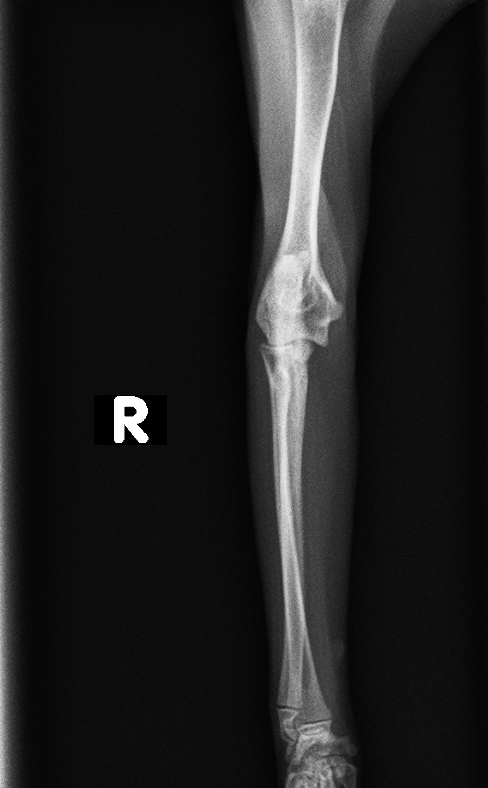

レントゲン検査より、右肘頭骨折が認められた

before